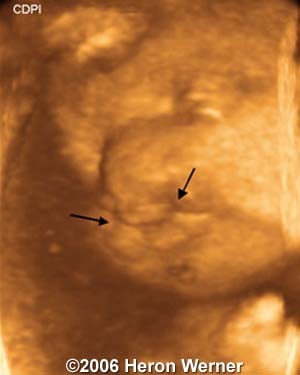

Coronal view shows bilateral cleft lip (arrows)